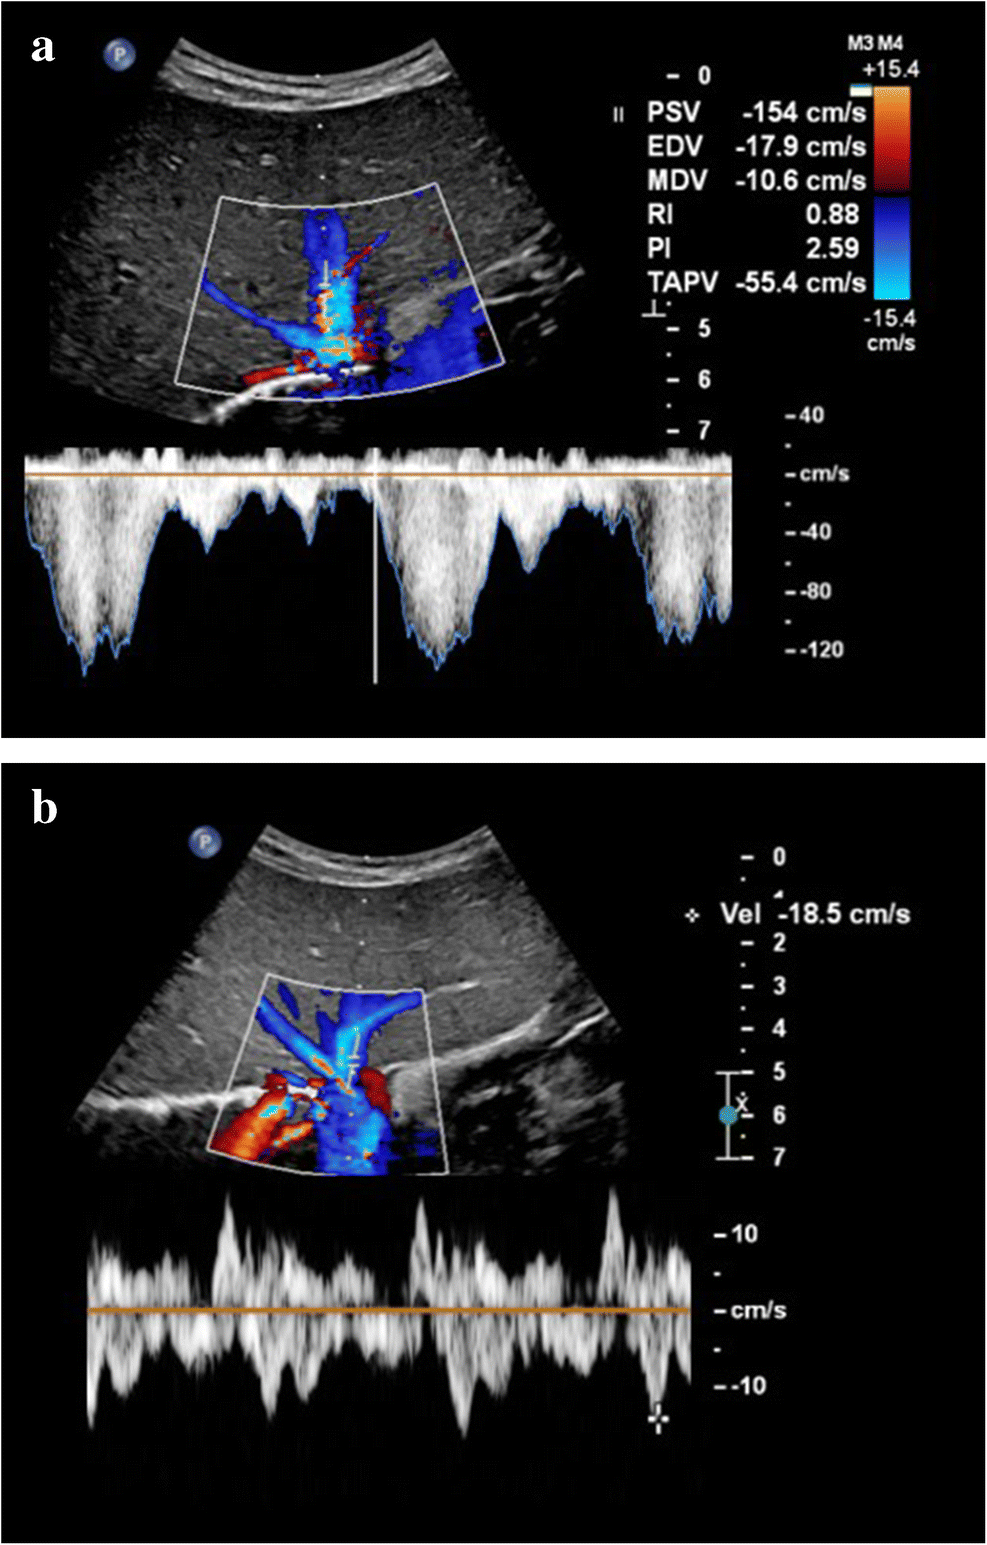

From our personal experience, hepatic vein peak systolic velocity can increase in the subclinical or early stages as well as during the course of sinusoidal obstruction syndrome, with peak velocities sometimes exceeding 120 cm/s and normalizing as the clinical condition improves (Fig. 4). To our knowledge, this US feature has not been studied extensively yet. Park et al. [26] found that peak velocity in the hepatic vein was somewhat higher in their veno-occlusive disease group compared with the non-veno-occlusive disease group (42.2±15.8 cm/s vs. 38.7±17.8 cm/s, respectively, P=0.23). Since we also encounter increased portal vein flow velocities and increased hepatic artery flow velocities in the early or subclinical course of sinusoidal obstruction syndrome, we hypothesize that an initial compensatory hemodynamic mechanism of the liver precedes clinical sinusoidal obstruction syndrome and the well-established Doppler imaging features (Table 2).

Fig. 4

Increased hepatic vein velocities during sinusoidal obstruction syndrome in a 3-year-old with stage 4 neuroblastoma treated with high-dose busulfan/melphalan followed by autologous stem cell transplantation who developed severe sinusoidal obstruction syndrome for which defibrotide was administered. a An intercostal transverse ultrasound (US) image shows how hepatic vein flow reached very high peak velocities of 154 cm/s during the sinusoidal obstruction syndrome episode, with coinciding high portal vein velocities of 40 cm/s (not shown). b An intercostal transverse US image shows how hepatic vein velocities normalized during follow-up with peak velocities of up to 18.5 cm/s. Hepatic vein flow velocites also normalized